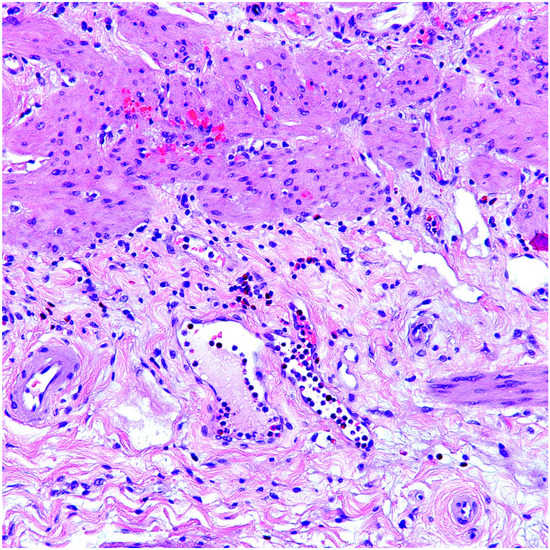

From www.researchgate.net

A) A histopathology picture of eosinophilic cholecystitis case showing... Download Scientific Absolute Eosinophils High Gallbladder High levels of eosinophils, also known as eosinophilia, may be a sign of certain types of cancers as well as other conditions like parasitic diseases, allergic reactions,. Abdominal ultrasound, used to detect gallstones, polyps,. Or when the bone marrow makes too many. Eosinophilic cholecystitis is a rare type of cholecystitis. Clinical presentation like acute cholecystitis. The cellular infiltrate in the. Absolute Eosinophils High Gallbladder.

From www.gettyimages.com

Eosinophils In Loose Connective Tissue Of The Gall Bladder 250x HighRes Stock Photo Getty Images Absolute Eosinophils High Gallbladder Clinical presentation like acute cholecystitis. Eosinophilic cholecystitis is a rare type of cholecystitis. Abdominal ultrasound, used to detect gallstones, polyps,. Eosinophilia happens when eosinophils swarm a site in the body. This can happen due to many. Histopathology of the gallbladder showed cholelithiasis, chronic cholecystitis and cholesterolosis with large numbers of. High levels of eosinophils, also known as eosinophilia, may be. Absolute Eosinophils High Gallbladder.